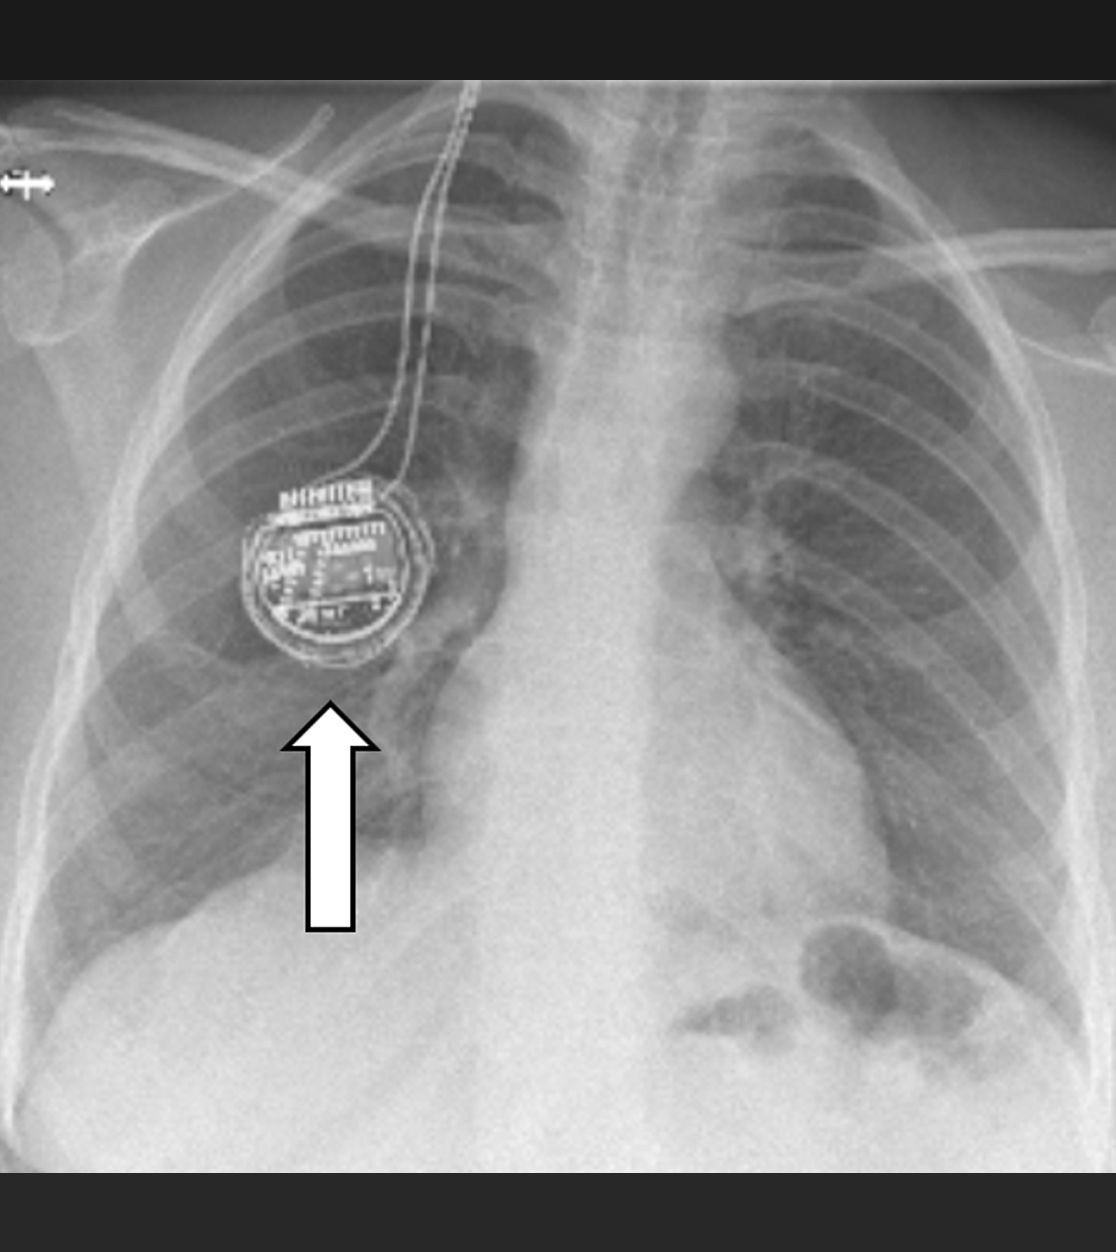

Am Bauch implantierte Medikamentenpumpe (Pfeil)

Impulsgeber im Bereich des Brustkorbs